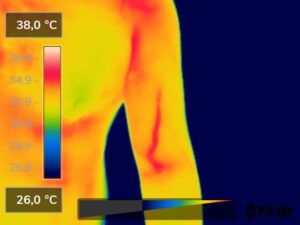

Como na sequência de termogramas abaixo de um paciente do sexo masculino, de 44 anos, sem comorbidades e praticante de atividade física que apresentou fortes dores em braço esquerdo (com irradiação para antebraço) após treino de musculação. Esta dor chegou a ser incapacitante, pois impossibilitava inclusive o paciente a realizar atividades de vida diárias como pegar um copo de água.

Após a realização de uma Análise Termofuncional©®, foi detectado alterações térmicas em “linha”, margeando as fibras musculares e tendíneas inferiores (insercionais) bicipitais. Estas alterações também aventaram a hipótese de dilatação venosa, por alguma reação inflamatória local. Foi realizado então aplicação de laserterapia através da Técnica Termoguiada, que acabou por promover a completa analgesia em 24 horas após aplicação.